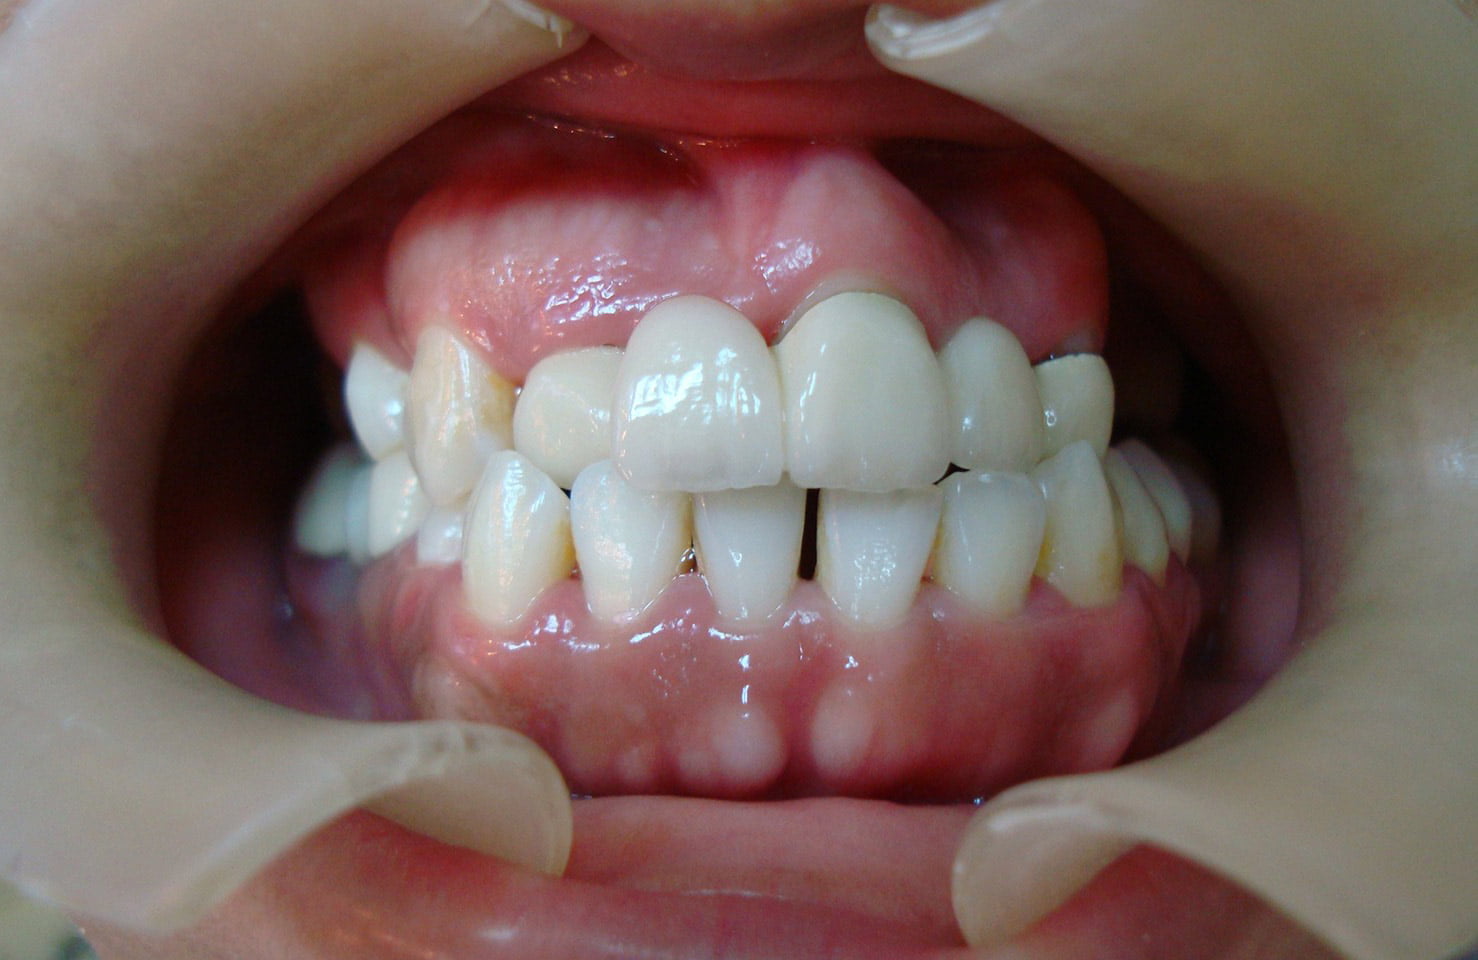

牙齒矯正